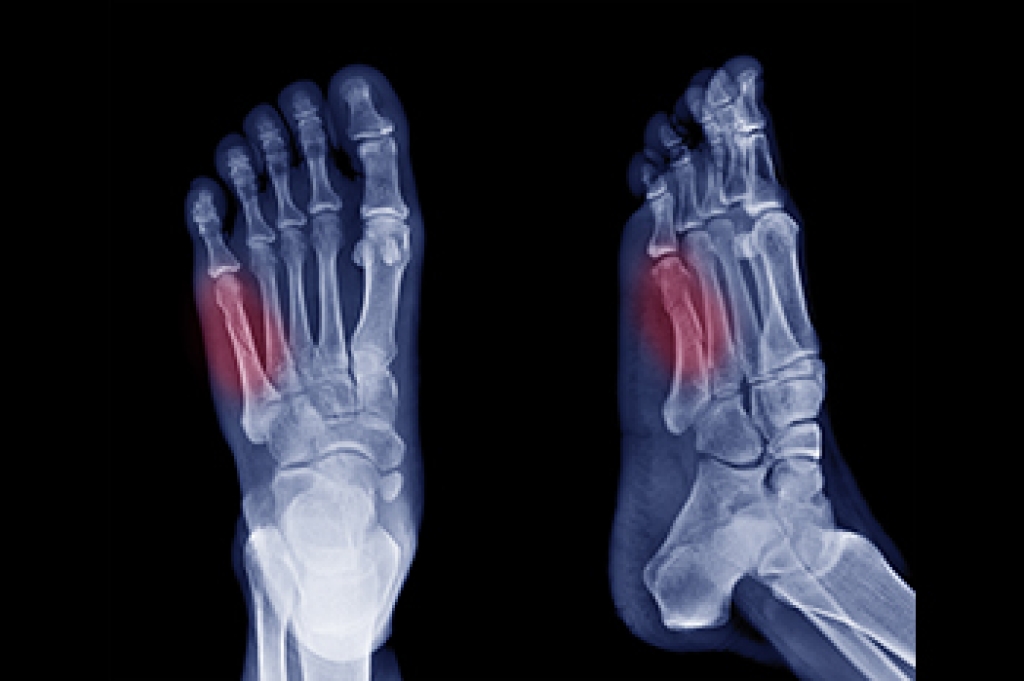

What Are Foot Blisters?

A foot blister is a small fluid-filled pocket that forms on the upper-most layer of the skin. Blisters are filled with clear fluid and can lead to blood drainage or pus if the area becomes infected.